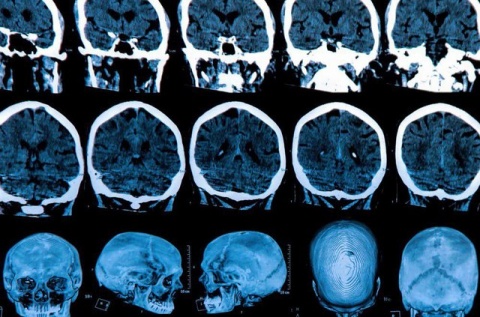

توالی‌های تکراری RNA های خاموشگر یافت شده در آسیب شناسی هانتیگتون بسیار شبیه به ملکول‌های RNA های خاموشگر کشف شده در مطالعه پیشین تیم بودند. بنابراین گام بعدی آزمایش این بود که آیا این ملکول‌های خاص هنگامی که از طریق نانوذرات به  بدن موش‌ها منتقل شدند، واقعا برای کشتن سلول‌های سرطانی کار می کردند یا خیر. نتیجه باورنکردنی بود، رشد تومور به طور قابل توجهی در انواع مختلف سلول‌های سرطانی، از جمله سرطان تخمدان، پستان، پروستات، کبد، مغز، ریه، پوست و سلول‌های سرطانی روده بزرگ، کاهش یافت.